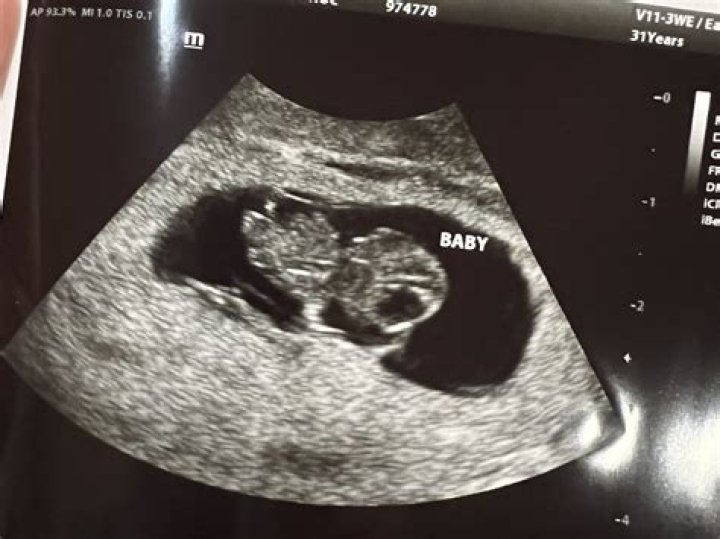

Pregnant Halsey shared the cutest ultrasound photo of her baby's feet in utero! See the sweet snapshot and get details.